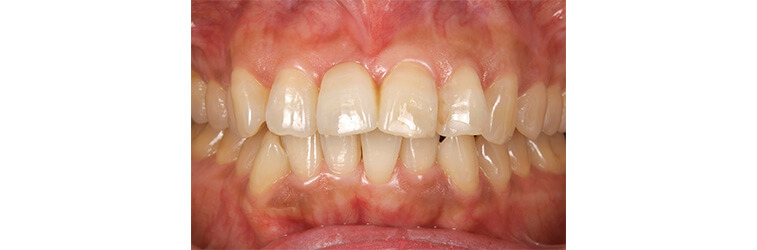

上の前歯の古い被せ物を治したいと言うことで来院されました。上下の前歯は少しガタガタになっており、奥歯には古い金属の詰め物が見られます。

上の前歯の被せ物が長い期間保つようにするためには、下の前歯のガタガタを整えておく必要があります。この症例くらいのガタガタであれば、インビザラインGoを使えば短期間で綺麗に治すことができます。歯並びが整ったことで治療のモチベーションが上がり、ホワイトニングと奥歯の銀歯を全てセラミックに置き換える治療を行い、金属がない(ノンメタル)状態になりました。